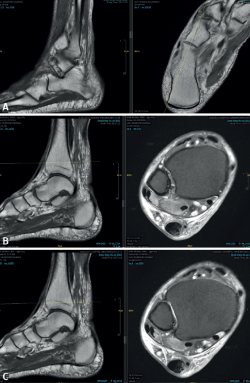

Se realizó una osteotomía medializante con efecto varizante de calcáneo (tipo Koutsogiannis) fijada con 2 tornillos canulados, a la que se añadió una transferencia del tendón flexor digitorum longus (FDL), anclándose en el escafoides con un tornillo interferencial. Se asoció una plicatura y retensado del ligamento en hamaca (Figura 2) y se tomaron muestras del tendón degenerado para su estudio histopatológico, cuyo resultado mostró abundantes áreas de degeneración mixoide con escasa celularidad inflamatoria crónica y mínima fibrosis.

Figura 2. Intervención quirúrgica. A y B: localización del abordaje de la osteotomía del calcáneo con fijación con tornillos; C: localización de cabo proximal y distal del tendón del tibial posterior; D: tendón flexor digitorum longus (FDL); E: tornillo de interposición para anclaje del FDL en el escafoides; F: sutura del ligamento en hamaca.